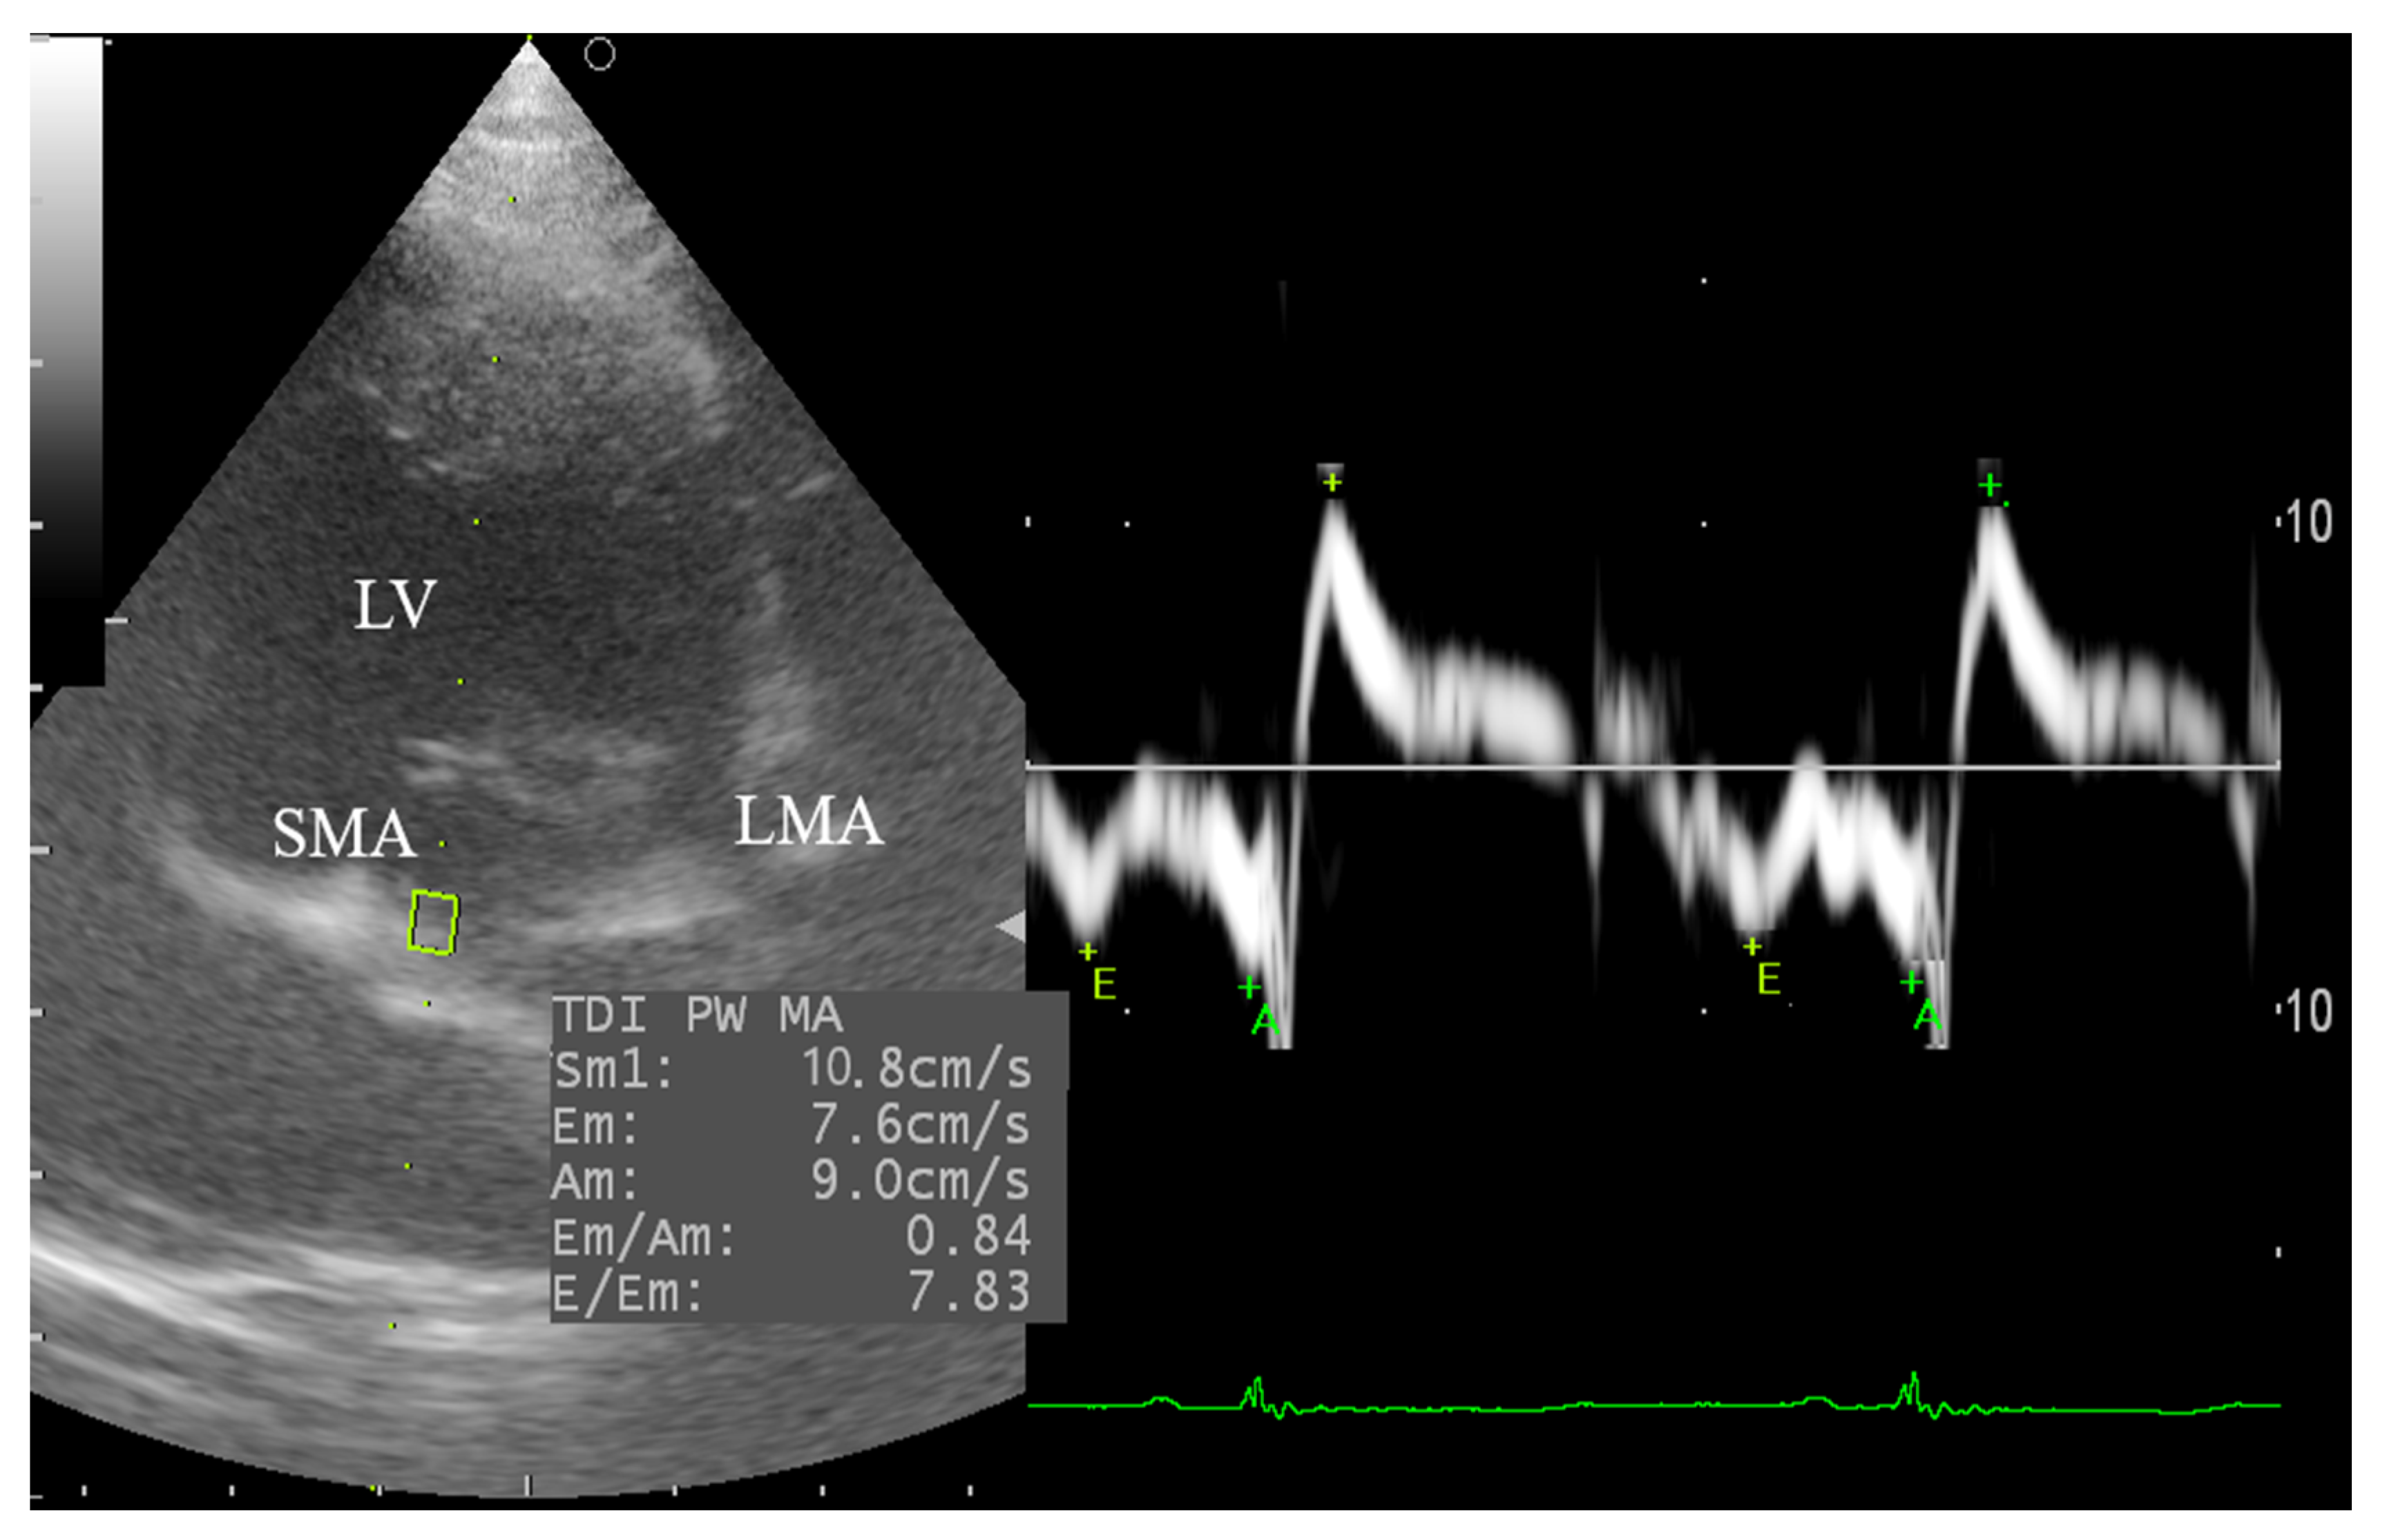

2.5. Tissue Doppler Imaging (TDI)

3.4.2. Tissue Doppler Imaging (TDI) of the Left Ventricular Wall

| Septal TDI | Sm # | cm/s | 10.61 | 1.006 | 0.041 | * | 9.48 |

| Em | cm/s | 7.852 | 1.642 | >0.10 | ns | 20.91 | |

| Am | cm/s | 8.447 | 2.465 | >0.10 | ns | 29.19 | |

| Em/Am | 1.024 | 0.375 | >0.10 | ns | 36.60 | ||

| Ev/Em | 6.548 | 1.087 | >0.10 | ns | 16.60 | ||

| Lateral TDI | Sm | cm/s | 13.52 | 2.974 | >0.10 | ns | 22.01 |

| Em | cm/s | 10.76 | 3.019 | >0.10 | ns | 28.06 | |

| Am # | cm/s | 9.978 | 2.167 | 0.002 | ** | 21.72 | |

| Em/Am | 1.122 | 0.372 | >0.10 | ns | 33.14 | ||

| Ev/Em | 4.938 | 1.251 | >0.10 | ns | 23.34 | ||

| Average TDI | Sm | cm/s | 12.06 | 1.505 | >0.10 | ns | 12.47 |

| Em | cm/s | 11.15 | 1.228 | >0.10 | ns | 11.01 | |

| Am | cm/s | 10.66 | 3.06 | >0.10 | ns | 28.70 | |

| Em/Am | 1.114 | 0.442 | >0.10 | ns | 39.66 | ||

| Ev/Em | 5.687 | 1.434 | >0.10 | ns | 24.92 | ||

| Pulsed-TDI | ||||

| Sm Sept # | cm/s | 10.5 ± 0.36 | 8.25 ± 0.38 | 0.00 * |

| Em Sept | cm/s | 8.5 ± 0.6 | 8.4 ± 0.4 | 0.97 |

| Am Sept | cm/s | 9.8 ± 1.1 | 6.7 ± 0.6 | 0.03 * |

| Em/Am Sep | 1.0 ± 0.2 | 1.3 ± 0.1 | 0.04 * | |

| Ev/Em Sept | 6.7 ± 0.6 | 5.6 ± 0.3 | 0.06 | |

| Sm Lat | cm/s | 13.52 ± 1.05 | 9.48 ± 0.66 | 0.00 * |

| Em Lat | cm/s | 12.5 ± 0.4 | 10.7 ± 0.5 | 0.03 * |

| Am Lat # | cm/s | 11.4 ± 1.4 | 8.6 ± 0.6 | 0.23 |

| Em/Am Lat | 1.3 ± 0.2 | 1.3 ± 0.1 | 0.81 | |

| Ev/Em Lat | 4.6 ± 0.5 | 4.5 ± 0.3 | 0.83 | |

| Average TDI | ||||

| Sm | cm/s | 12.06 ± 0.53 | 8.79 ± 0.48 | 0.00 * |

| Em | cm/s | 11.15 ± 0.43 | 9.57 ± 0.42 | 0.06 |

| Am | cm/s | 10.66 ± 1.08 | 7.66 ± 0.48 | 0.02 * |

| Em/Am | 1.11 ± 0.16 | 1.32 ± 0.12 | 0.18 | |

| Ev/Em | 5.69 ± 0.51 | 5.05 ± 0.24 | 0.28 | |